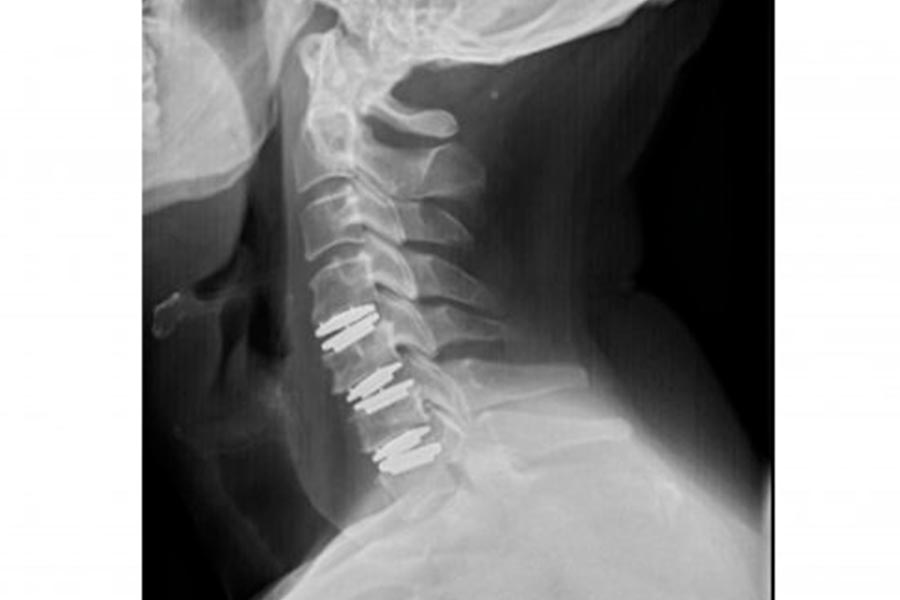

En este caso clínico, los especialistas del Instituto de Cirugía Avanzada de Columna intervienen a una paciente joven mediante artrodesis cervical.

Es un caso de cirugía cervical de una paciente de mediana edad que fue operada hace aproximadamente 6 años.

La paciente presenta varias hernias discales cervicales, empeoradas por la presencia de artrosis en la zona y que provoca dolencias en el lado derecho (brazos y cuello).

El paciente acude a la consulta tras sufrir fuertes dolores en la zona, provocados por una artrodesis no efectiva. Implante de prótesis cervical.

Caso de extrema dificultad en el que podemos ver a un paciente con dolor crónico cervical, parentesias MMSS y hormigueo en los miembros superiores.

Nos encontramos ante un paciente con dolor agudo que presenta tres hernias discales cervicales. Su situación no mejoraba con medicación ni tratamiento.